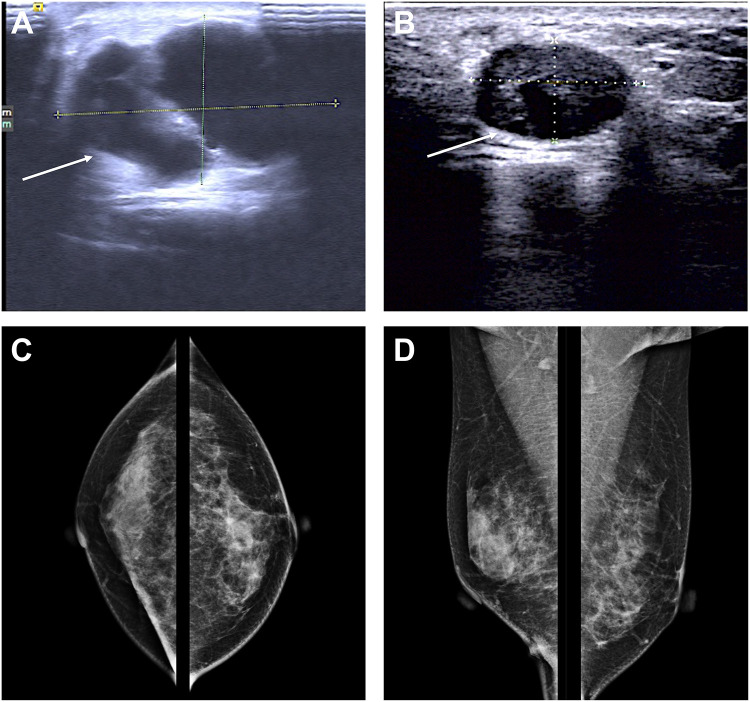

Epithelial-myoepithelial carcinoma (EMC) of the breast is a rare biphasic tumor composed of intermixed malignant epithelial and myoepithelial components. Breast epithelial myoepithelial carcinoma lacks therapeutic strategies due to its rarity, and currently local treatment is still the main treatment. Herein we report an epithelial-myoepithelial carcinoma of the breast in a 33-year-old woman undergoing breast conserving surgery, sentinel lymph node biopsy, adjuvant chemotherapy and radiotherapy, with rapid liver and lung metastasis. After radiofrequency ablation therapy for metastatic lesions, vinorelbine plus cisplatin and TROP2 antibody-drug conjugate (ADC) treatment were given successively. After a brief improvement, drug resistance developed and the disease progressed. The patient died with the PFS 5.6 months.